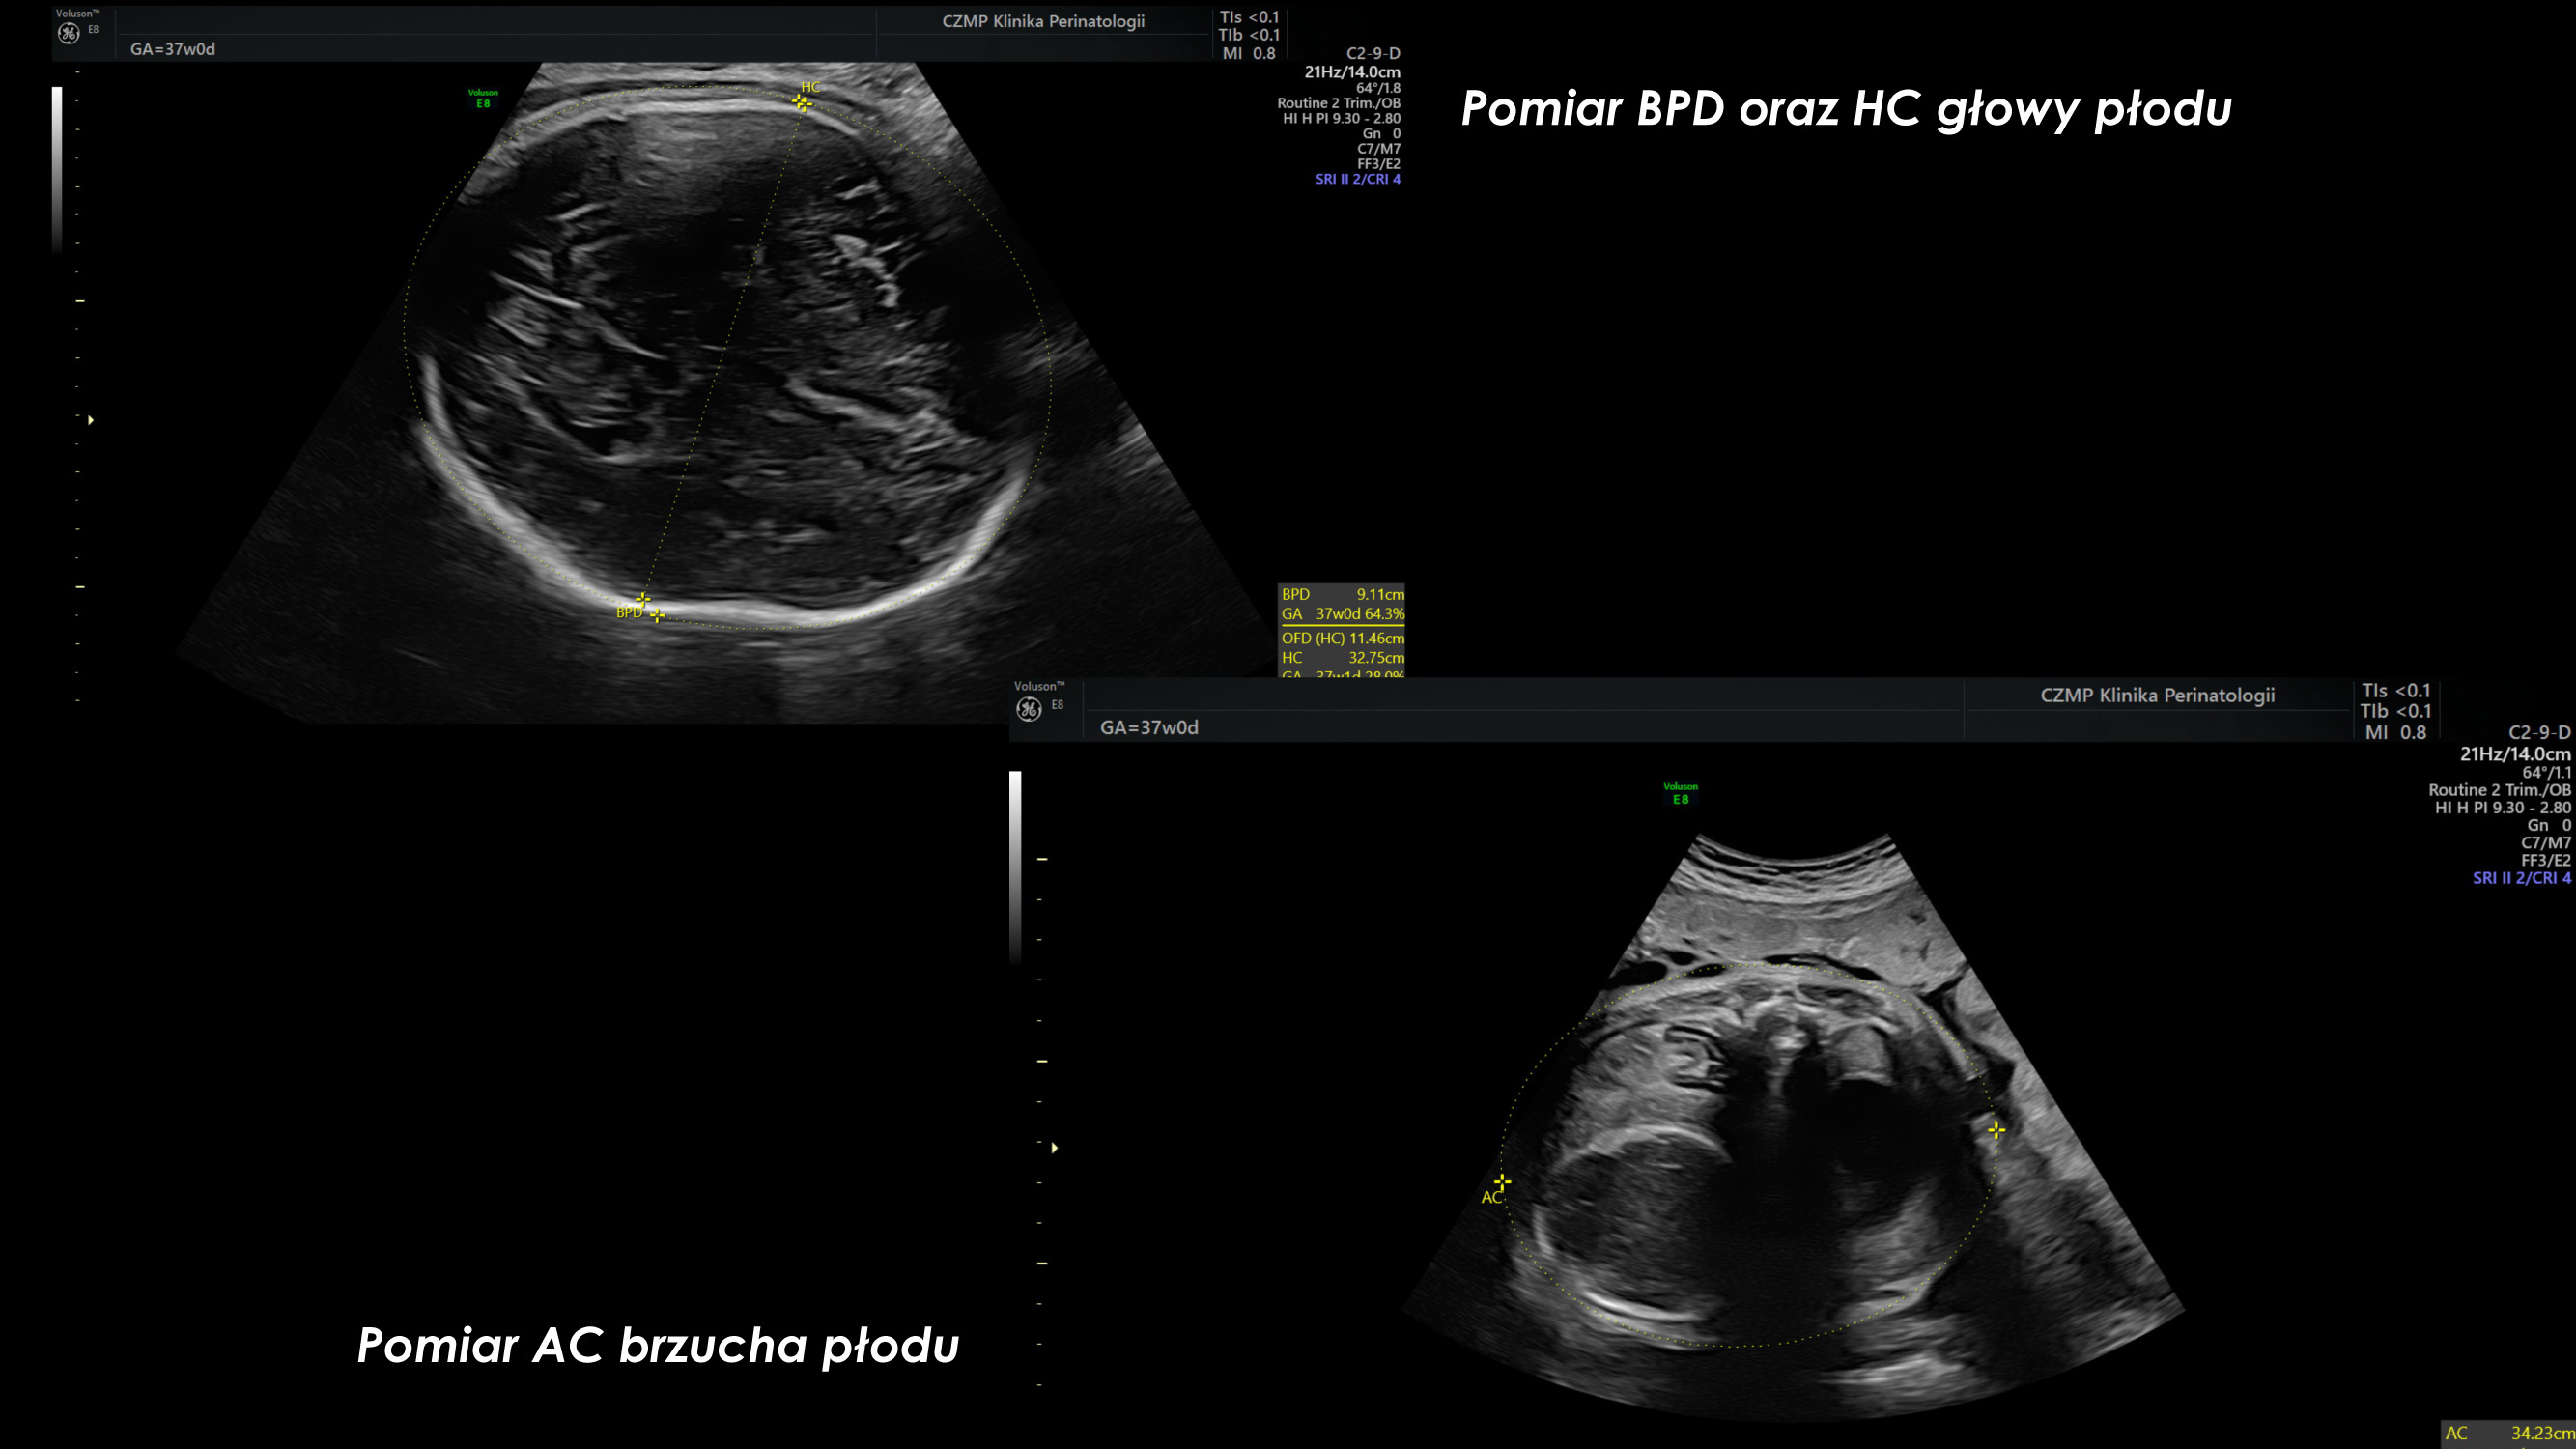

Nietypowy guz jamy brzusznej płodu